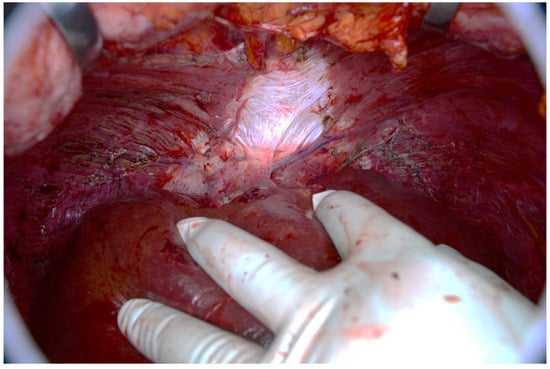

Figure 10. Ruptured mucocele of the appendix in perioperative view. Part of the appendix (black arrow) is embedded in mucus (white arrow), which covers the perforation.

The mucocele ruptures due to increased intra-appendicular pressure, releasing mucus and tumor cells into the peritoneal cavity (Figure 9 and Figure 10). The rupture may be asymptomatic or associated with only mild and nonspecific clinical signs. Typical peritoneal signs and bacterial peritonitis are usually absent because the communication to the lumen of the colon is closed by mucin. Treatment in these cases is called a radical appendectomy, with the resection of the cecal bases, but without a right colectomy. The addition of HIPEC is fully indicated. It is necessary to examine the whole abdomen to exclude the presence of tumors in typical locations, such as the Douglas pouch and the undersurfaces of the diaphragm and the right and left paracolic gutter.